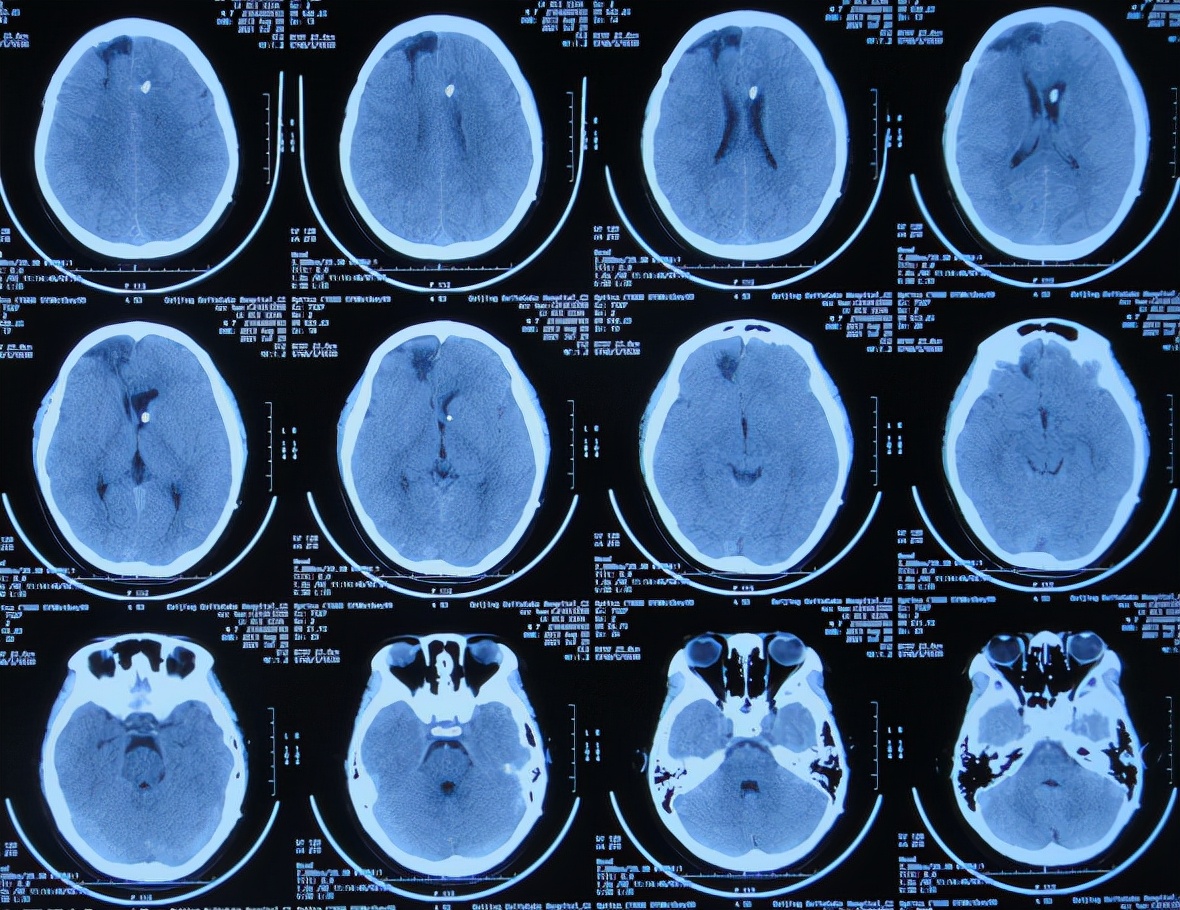

次日即2021年3月24日,转入该院的神经外科,仍发热体温高达38.0-39.0℃,查脑CT示出现水肿,仍有出血( 图-3 ),给予抗感染治疗。

图-3: 2021年3月24日脑CT

腰大池引流术后3天即2021年4月2日,脑脊液白细胞仍高,患者仍持续发热,查脑CT示仍有积水和水肿( 图-4 )。

图-4: 2021年4月2日脑CT

腰大池引流术后7天即2021年4月6日,体温降低至37.6℃,查脑CT示脑室缩小( 图-5 );遂拔除了腰大池引流管。

图-5: 2021年4月6日脑CT